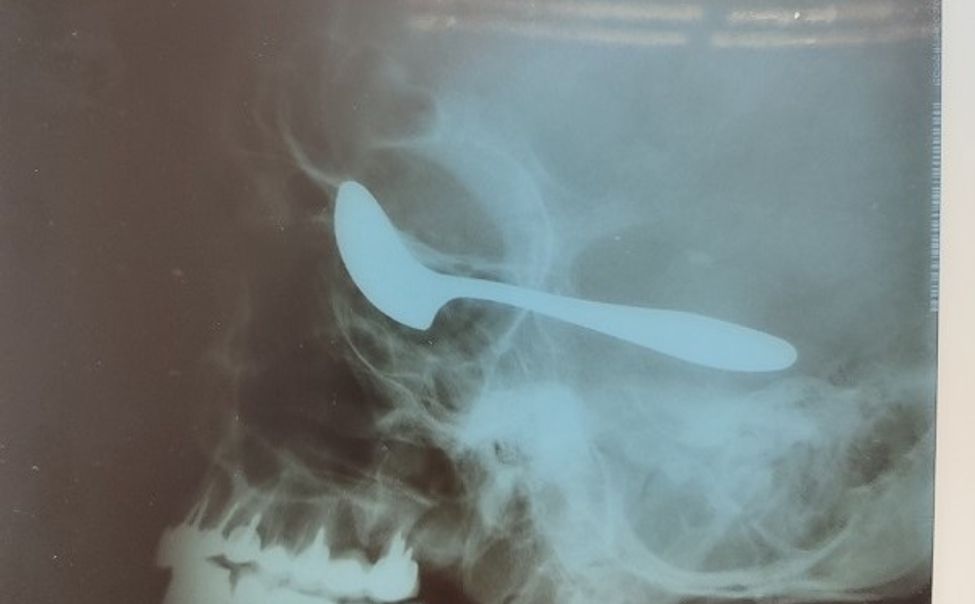

В Чувашии пациент с белой горячкой загнал себе ложку в глаз

Хирурги Алатырской ЦРБ и РКБ спасли жизнь и сохранили зрение пациенту с травмой глаза.